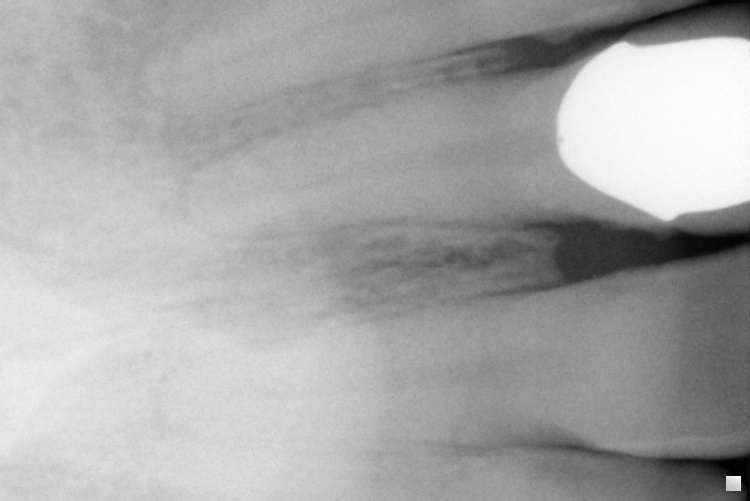

[PARENTDIR] Parent Directory - [IMG] IO000001.jpg 2020-07-28 14:17 77K [IMG] IO000002.jpg 2020-07-28 14:17 79K [IMG] IO000003.jpg 2020-07-28 14:17 82K